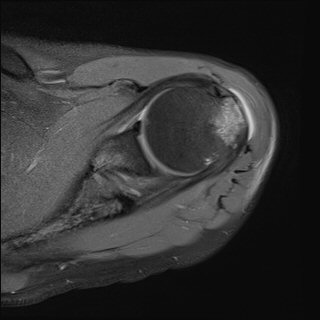

ÀÚ±â°ø¸í°Ë»ç

»ó¿Ï°ñµÎ ´ë°áÀý °ß¿­°ñÀý